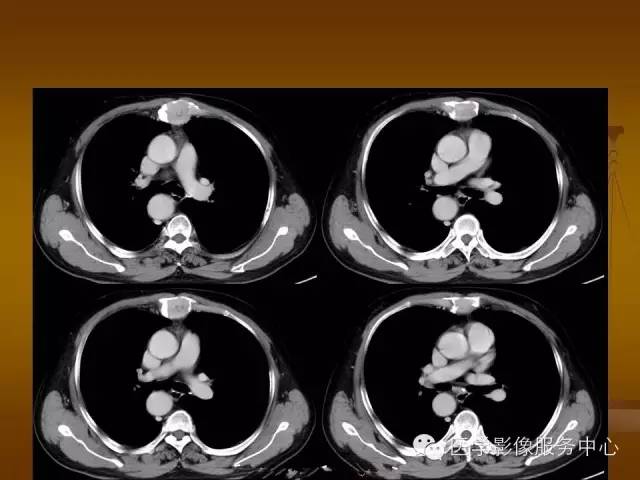

增强扫描可见病灶轻中度强化,一般于静脉期达峰值。

1、 软骨瘤:胸骨很常见,其在CT上表现为环状或分房状膨胀性生长,骨皮质完整,不侵犯邻近组织,软骨瘤可发生恶变。

2、 胸骨转移瘤:溶骨性骨质破坏与邻近软组织肿块,有报道仅乳腺癌胸骨转移可为成骨性转移。

3、 胸骨肿瘤样病变:嗜酸性肉芽肿的表现为膨胀性或溶骨性骨质破坏,内部可见点状死骨,一般边界清楚,无硬化,可穿破胸骨前后骨皮质形成较薄的软组织肿块;增强扫描肿块轻、中度强化,强化均匀,一般无坏死;发生于胸部一般无骨膜反应。